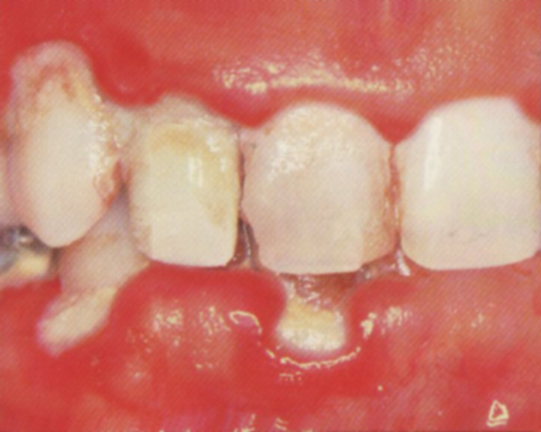

Advanced periodontitis

- gum boils or abscesses may develop

- teeth may become mobile or loose

- bad breath and bad taste are constant

- roots may be exposed and are sensitive to hot and cold

- severe horizontal and angular bone loss on X-Ray

- pockets between teeth and gums now in excess of 6 mm deep